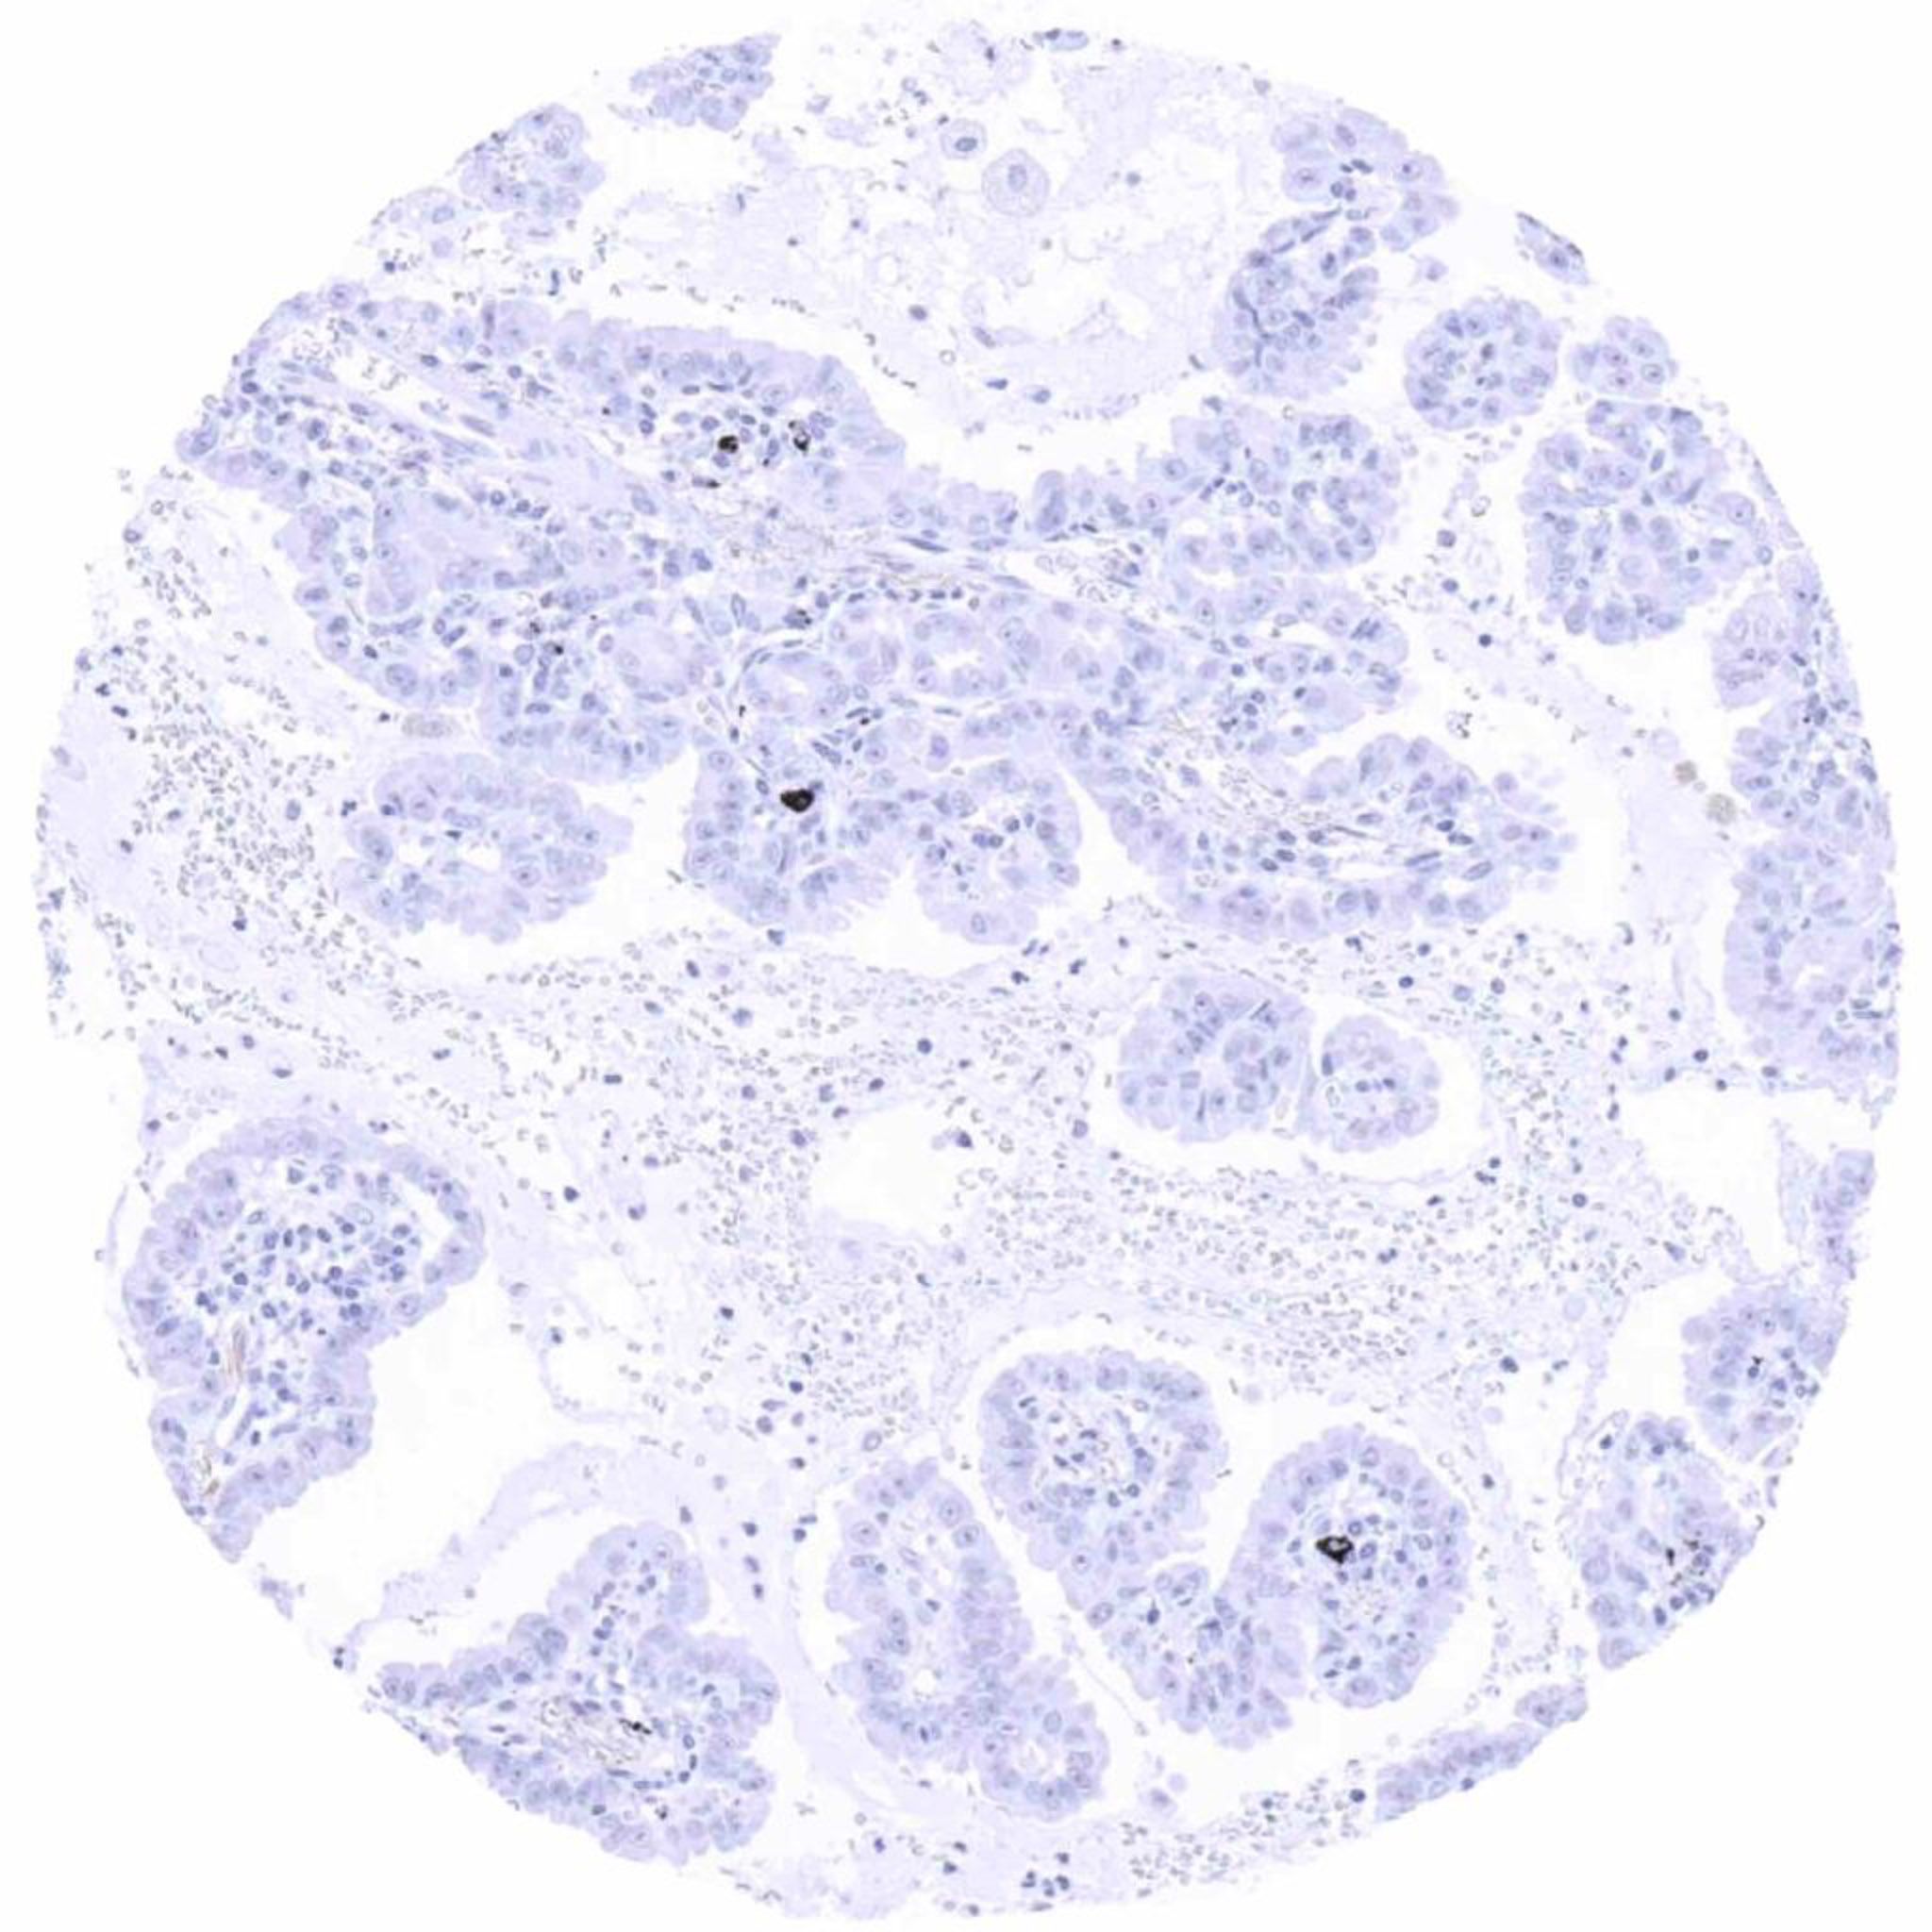

Ovary – Serous high-grade carcinoma with strong membranous UPK3B immunostaining in a subset of tumor cells

Ovary – Serous high-grade carcinoma with strong membranous UPK3B staining in _80_ of tumor cells

Ovary – Serous high-grade carcinoma with strong membranous UPK3B staining of a subset of tumor cells

Ovary – Serous high-grade carcinoma with strong UPK3B positivity of luminal membranes of a fraction of tumor cells